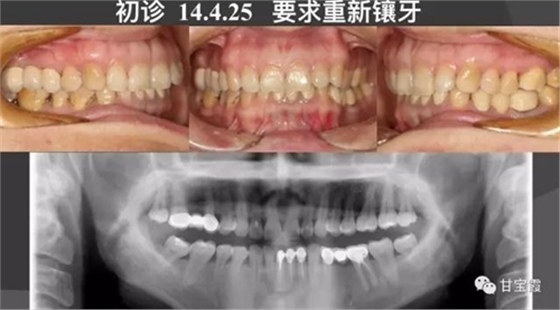

一位33歲女性患者,由朋友介紹來(lái)我診所鑲牙,初診檢查發(fā)現(xiàn)她牙弓形態(tài)不好看,還缺兩顆牙,幾年前曾經(jīng)鑲過(guò)九顆烤瓷牙,如下圖所示,如今口腔有異味,要求重新鑲牙。

大家都知道以前缺一顆牙要鑲?cè)w烤瓷牙,缺兩顆要鑲六顆烤瓷牙,因而好好的一顆牙就因?yàn)殍偲渌辣荒サ袅艘粚樱挚上?。這次就診根據(jù)患者口腔的檢查我制定了一個(gè)治療計(jì)劃:拆除九顆烤瓷牙,缺牙的部分用正畸的方法移動(dòng)牙齒,關(guān)閉缺牙間隙,不再鑲牙。下前牙的三顆聯(lián)排的烤瓷牙改成單顆修復(fù),這樣更符合生理。下面的系列圖片是治療過(guò)程,大家可以看到缺牙間隙是怎么一點(diǎn)一點(diǎn)關(guān)閉的。